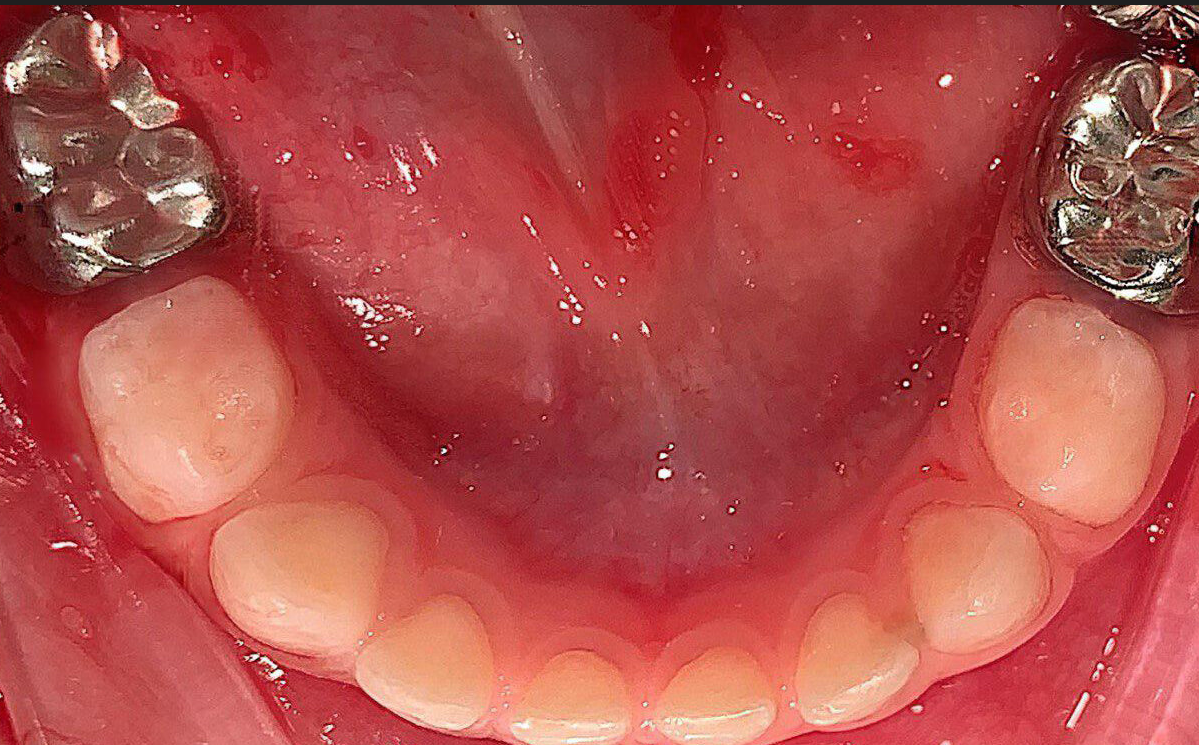

Ви знали про те, що молочні зуби теж можуть мати коронки. Сталеві коронки є одним з найкращих засобів захисту та відновлення молочних зубів. Застосовуються дитячі коронки у маленьких пацієнтів із високою схильністю до розвитку карієсу та при дуже великих каріозних ураженнях.

Коронки на молочні моляри виготовлені зі сталі. Вони бувають різних розмірів та підганяються залежно від індивідуальних розмірів зуба.

Установка коронки відбувається швидко, під час процедури дитина відчуває лише тиск. За один-два дні дитина адаптується до нової ситуації в порожнині рота шляхом посиленого прикусу, після чого дискомфорту вже не відзначає.